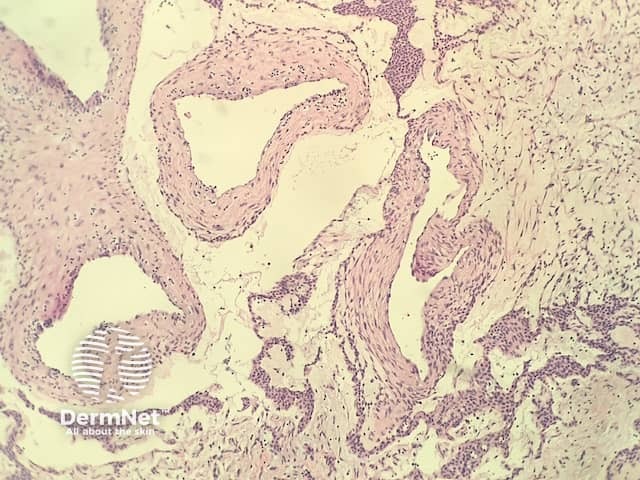

In glomangioma, the histopathology shows dilated venous channels that resemble venous malformations (figures 1, 2). Unlike venous malformations, they demonstrate single to multiple rows of surrounding cuboidal glomus cells (figures 3,4).

Figure 1